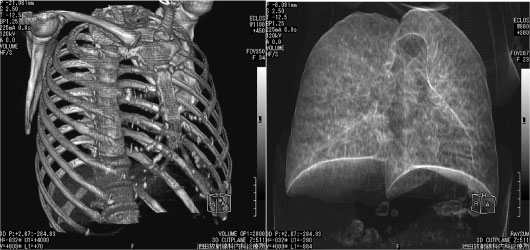

画像 1 検診で右中下肺野の異常陰影を指摘。同一視点から肺と骨性胸郭を分離して表示した。

肺内病変なく右肋骨に骨折痕。